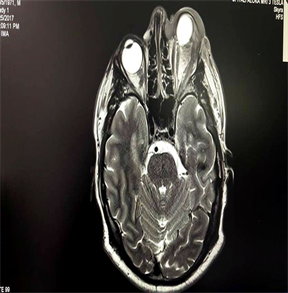

RTG pulmo had no significant changes. Cranio-orbital MRI revealed no intracranial involvement with suspicion of preseptal/orbital cellulitis and differential diagnosis for pseudotumor or lymphoma (Figure 3).

Figure 3. Initial Cranio-orbital MRI.

In meanwhile, the proptosis advanced with dislocation down and nasal, with no motility movement, no pupillary reaction, cornea exposal and amaurotic eye (Figure 5). Second cranio-orbital MRI revealed still no intracranial involvement, but morbid progression of the diseases (Figure 6).

Figure 6. Second Cranio-orbital MRI.